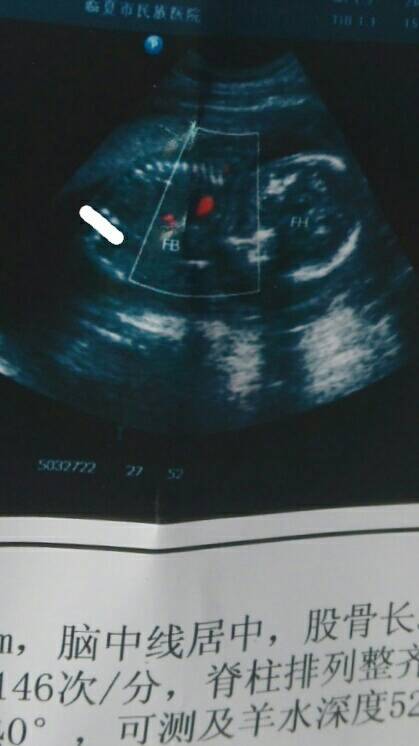

我五个月的时候照的,一直不明白两个白点是宝宝的什么,老公说他也看到两腿之间也有两个白点,是男是女 点击展开 匿名用户 2015-05-19 23:18 为您推荐: 其他回答 这图根本看不出来,只有去做b超的时侯看的比较清楚。 万俟傲薇_4dgI 2015-05-19 23:22 看的不是很清楚再说生殖器也不是白点 匿名用户 2015-05-19 23:22 相关问题 怀孕三个月十天两腿之间有四个白点是男孩还是女孩 孕3个月B超显示两腿之间有个白点,医生说是女孩,准么? 四维彩超宝宝两腿之间有白点,是不是男孩